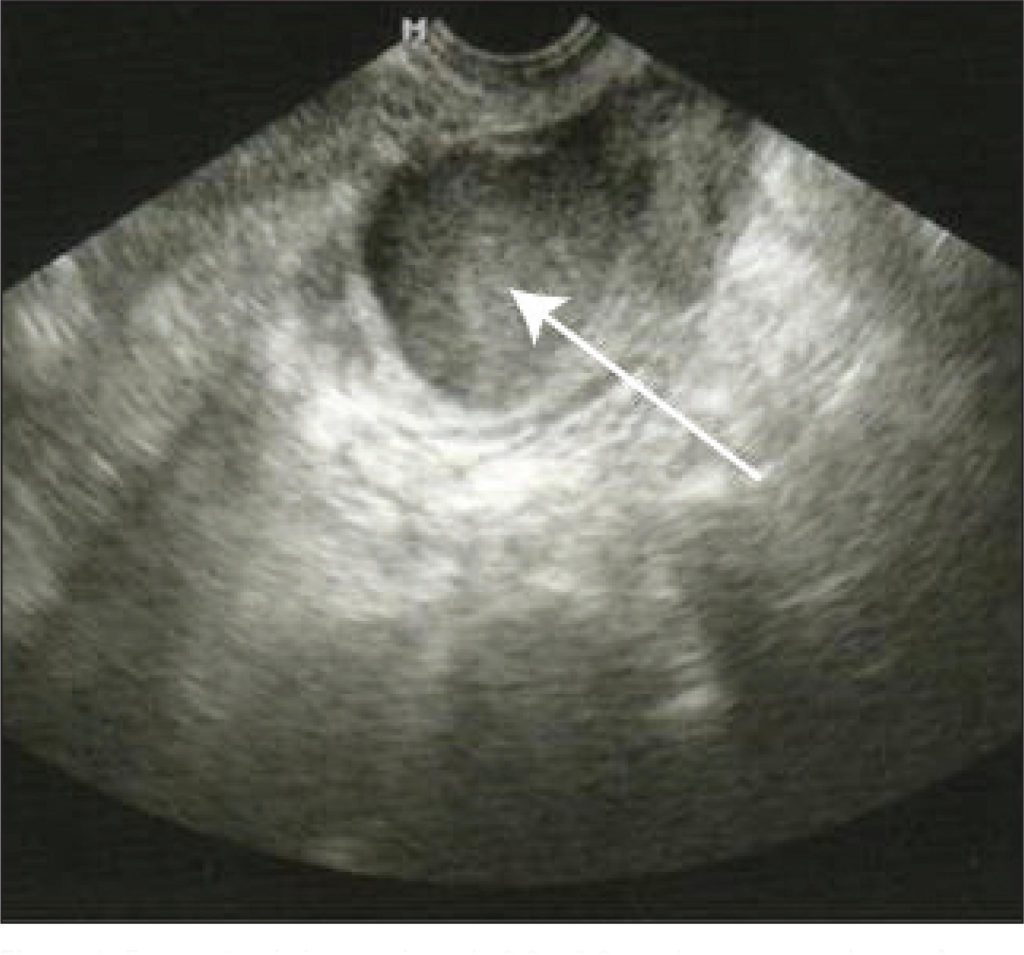

Foram estudadas 21 pacientes acompanhadas no ambulatório de reprodução humana com indicação de fertilização in vitro e diagnóstico laparoscópico de endometriose III ou IV que apresentavam endometrioma recidivado maior que 3 cm após a cirurgia. Foi realizado bloqueio prévio com análogo agonista de GnRH por pelo menos 20 dias, e os cistos foram submetidos à punção guiada por ultrassonografia e alcoolização subsequente. As pacientes foram estimuladas com 100 ou 200U/dia de hormônio folículo estimulante recombinante, com a dose variando de acordo com a idade ou ooforectomia unilateral prévia.

Os cistos ovarianos aspirados tinham em média 4,7 ± 1,4 cm e em nenhum caso a imagem se refez durante a indução da ovulação. A captação oocitária ocorreu, em média, após 11 dias de indução com 3,95 ± 3,30 oócitos por ciclo. Houve transferência embrionária em 71,4% (15/21) das pacientes, e a taxa de gravidez por transferência foi de 20% (3/15).